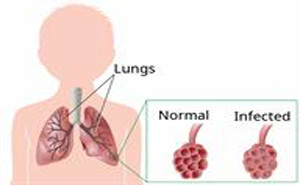

practice guidelines for community-acquired pneumonia (CAP).Community-acquired pneumonia

(CAP), an infection of the lung parenchyma that occurs in persons outside of a

hospital setting, is associated with high morbidity and mortality.&nb...

Community-acquired pneumonia (CAP)

is a significant cause of respiratory morbidity and mortality in children,

especially in developing countries. Worldwide, CAP is the leading cause of

death in children younger than five years.

Clinical assessment requires

careful evaluation of clinical features, severity, and evidence of

complications....